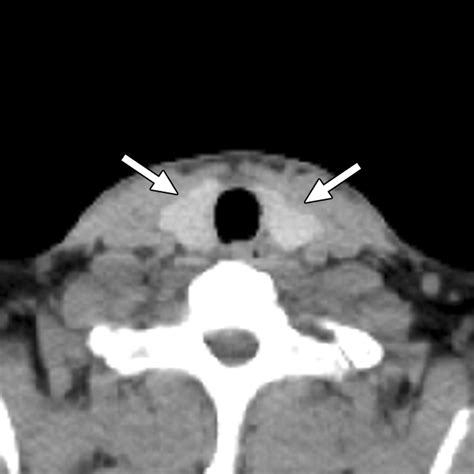

The thyroid gland is a small, butterfly-shaped organ located in the base of your neck, yet it exerts a profound influence over your body's metabolic rate, heart function, and energy levels. When you experience symptoms such as unexplained weight changes, fatigue, or visible swelling in the neck, a medical professional may recommend a scan thyroid gland procedure to gain a deeper understanding of your thyroid health. This diagnostic process is a safe and highly effective way to visualize the structure and function of the gland, helping doctors distinguish between benign conditions and more serious concerns.

A thyroid scan is typically ordered when blood tests indicate that your thyroid hormone levels—such as TSH, T3, or T4—are abnormal. It is not always the first step, but it is an essential tool for evaluating the underlying cause of thyroid dysfunction. By performing a scan thyroid gland, specialists can observe how much radioactive iodine your thyroid absorbs, which helps determine if the gland is overactive, underactive, or if there are structural irregularities like nodules or cysts.

Once the scan thyroid gland images are generated, an endocrinologist or radiologist will interpret the “uptake” patterns. The distribution of the radioactive tracer reveals how well the gland is functioning. A uniform distribution usually indicates a healthy, properly functioning gland. Conversely, areas with intense uptake—often called “hot nodules”—suggest that specific parts of the thyroid are working excessively, while “cold spots” might warrant further biopsy to rule out malignancy.

It is important to remember that these scans provide a “snapshot” of activity. They are best analyzed in conjunction with clinical physical exams and hormonal blood panels to form a comprehensive diagnosis. If a nodule is found to be “cold,” your doctor may suggest an ultrasound-guided fine-needle aspiration to get a definitive tissue sample.